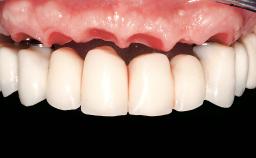

Prosthodontic SAC classification

| SAC Level | - |

|---|---|

| Defining Characteristics | - |

| Loading Protocol | - |

| Retention | - |

| Maxillomandibular Relationship | - |

| Mesio-Distal Space | - |

| Inter-Arch Distance | - |

| Bruxism | - |

| Esthetic Risk | - |

| Provisional Implant-Supported Prosthesis | - |

| Interim Prosthesis during Healing | - |

| Occlusion/Articulation | - |

| Occlusal Scheme/Issues | - |